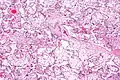

| Micrograph of villous immaturity. H&E stain. | |

Placental villous immaturity is chorionic villous development that is inappropriate for the gestational age.

Immature chorionic villi are larger and have more central blood vessels; thus, the diffusion distance for gas and nutrient exchange is larger and, therefore, placental function is impaired.